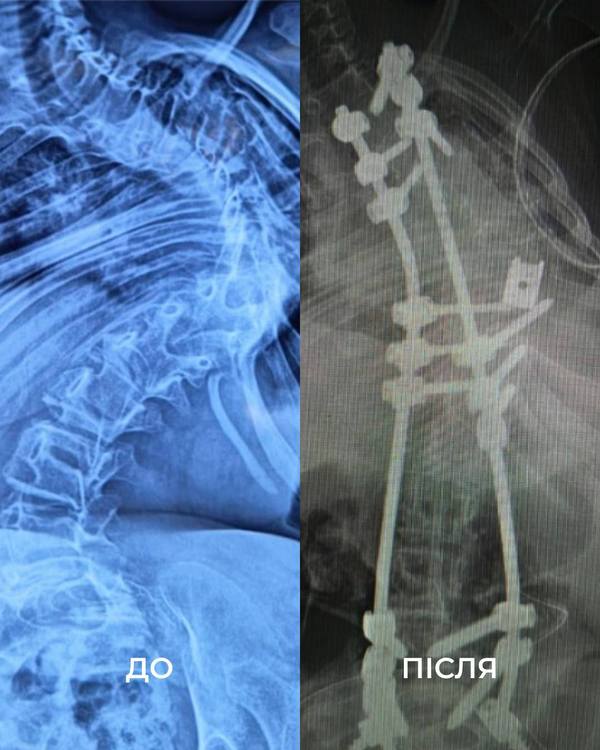

«Щоб виправити її сколіоз, нам потрібно було видалити цілий хребець. У перший день операції ми закріпили її хребет гвинтами. А потім уже на другий день видалили кілька ребер, ізолювали спинний мозок та встановили титанову клітку для підтримки хребта. А потім повільно виправляли її», — розповідає американський ортопед-травматолог Марк Диржка.

Після двох операцій, 18 годин наркозу та через надто слабкі м’язи два наступні тижні дівчинка пробула в реанімації під киснем. У результаті операцій хірургам вдалося вирівняти хребет дитини на 85%.